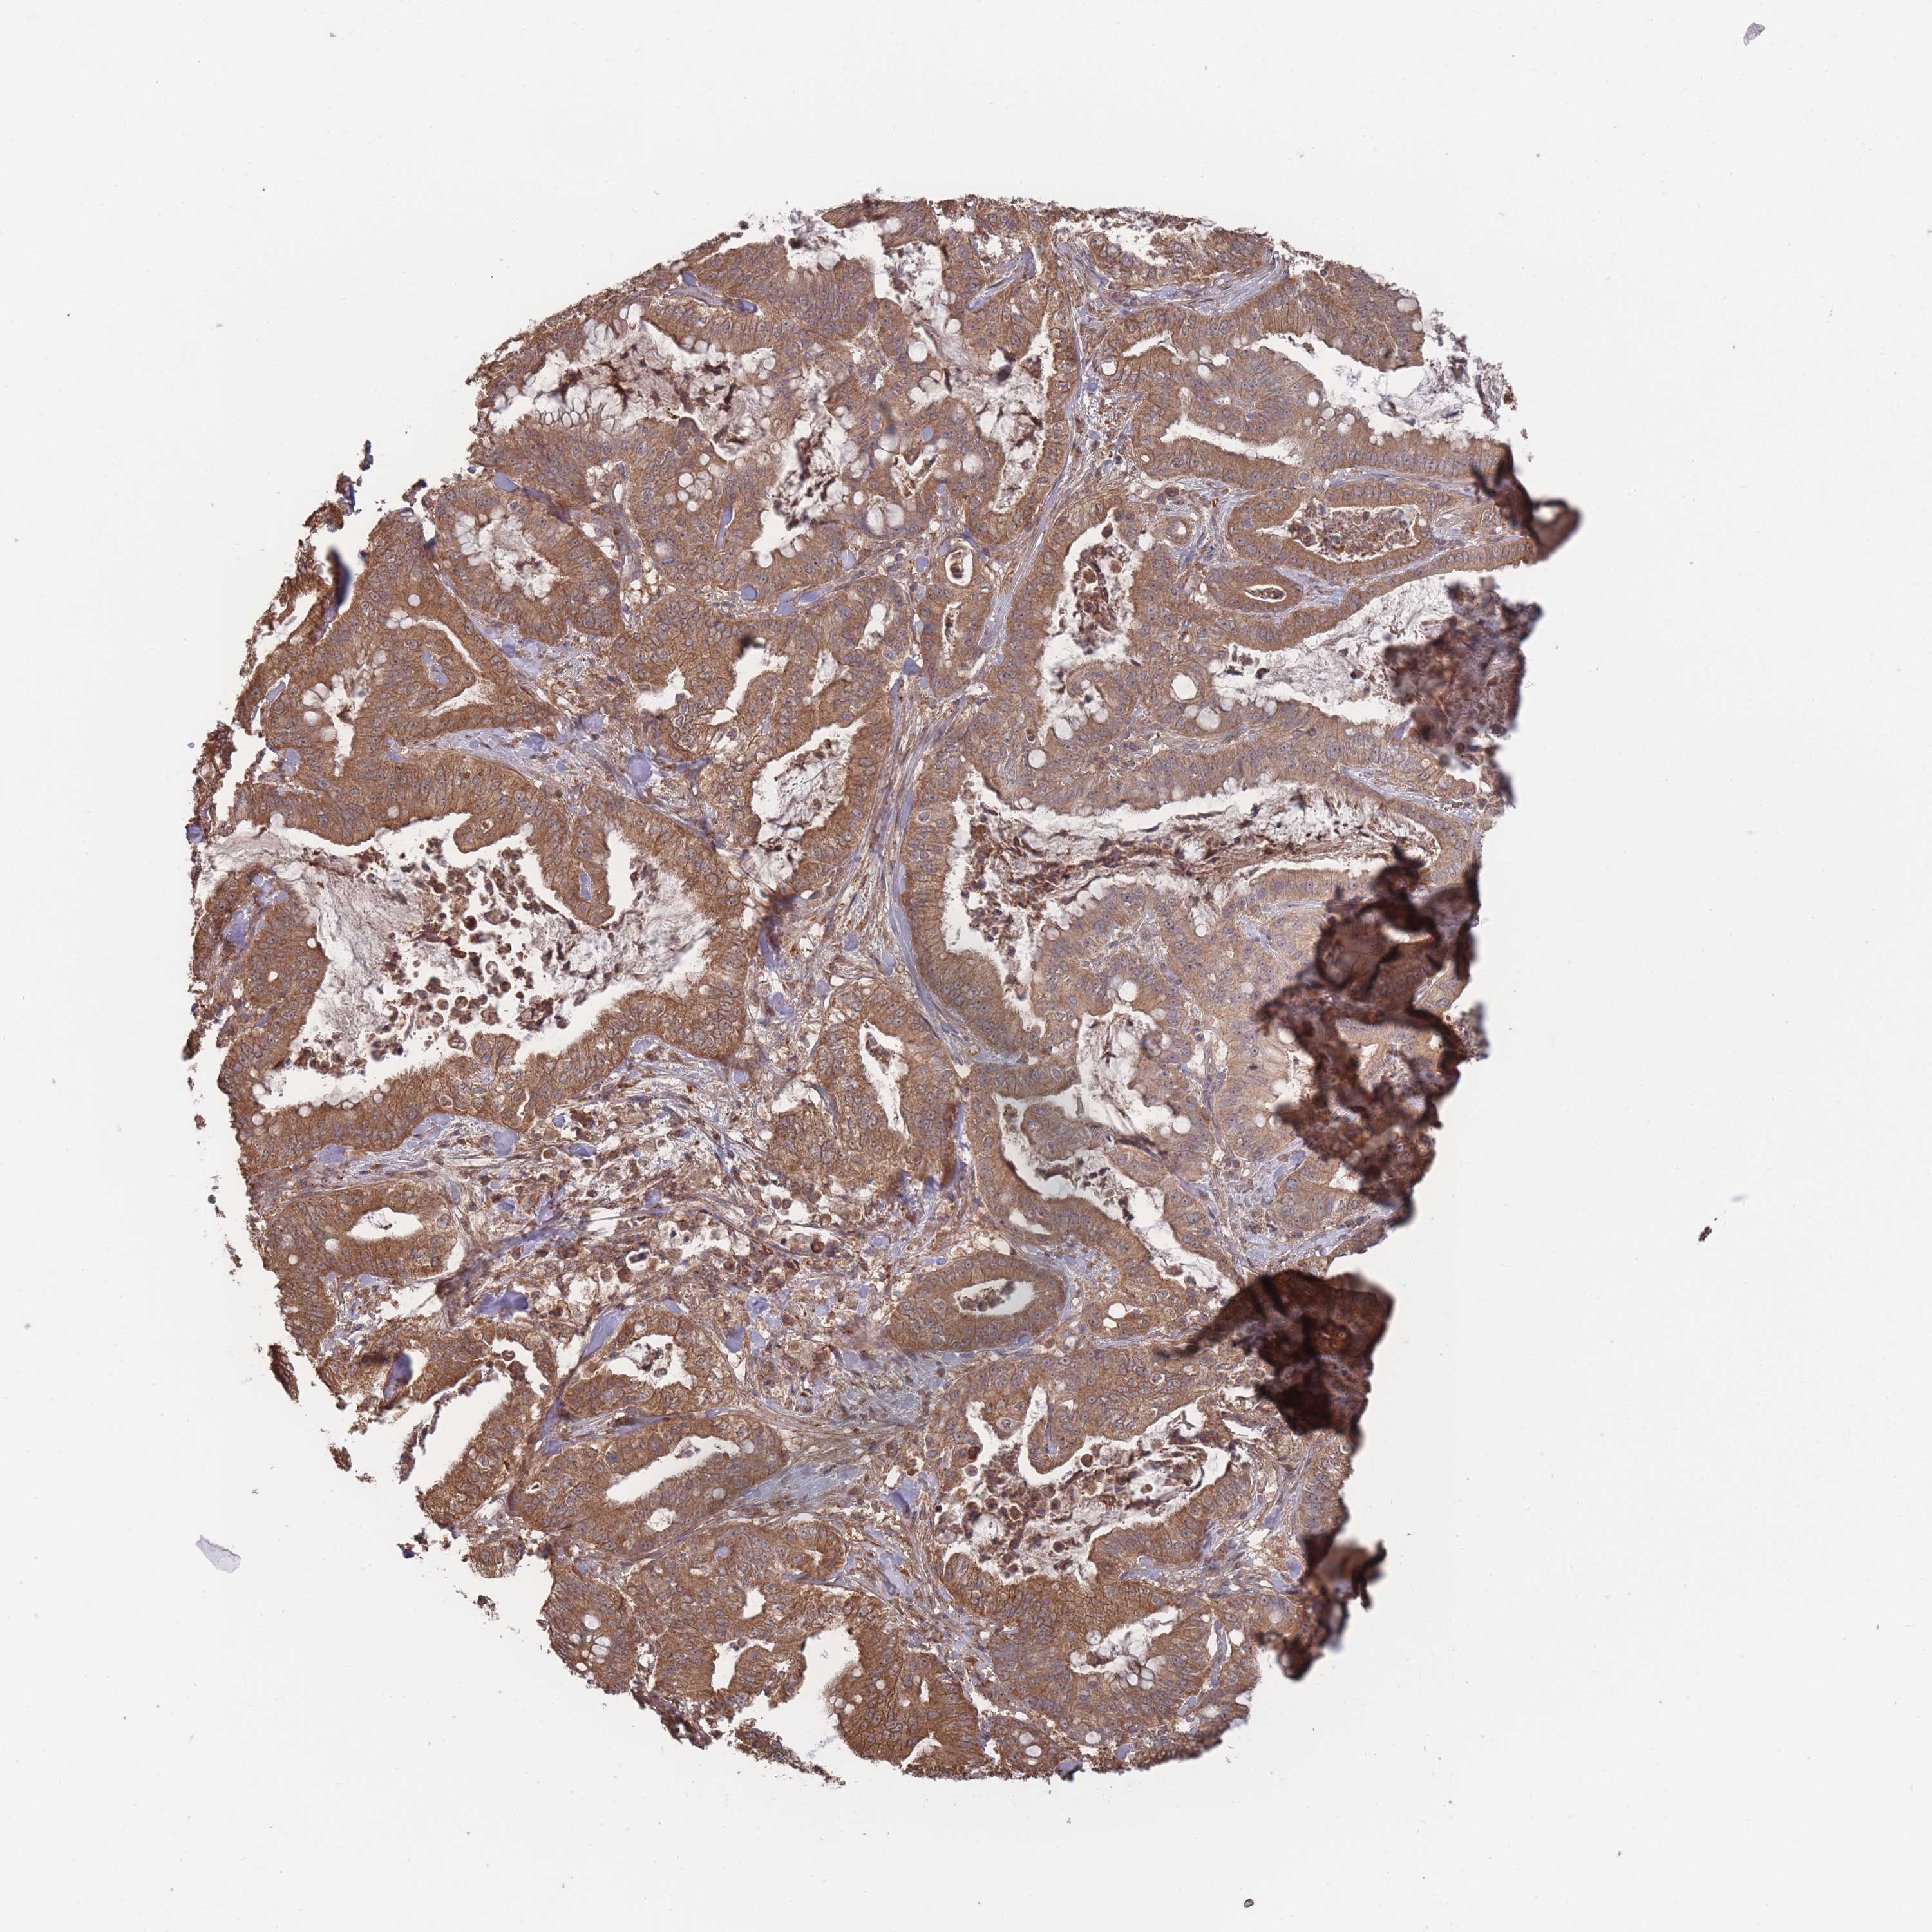

PANCREATIC CANCER - Protein expressioni

A mouse-over function shows sample information and annotation data. Click on an image to view it in a full screen mode. Samples can be filtered based on level of antibody staining by selecting one or several of the following categories: high, medium, low and not detected. The assay and annotation is described here.

Note that samples used for immunohistochemistry by the Human Protein Atlas do not correspond to samples in the TCGA dataset.

Antibody stainingi

Antibody staining in the annotated cell types in the current human tissue is reported as not detected, low, medium, or high, based on conventional immunohistochemistry profiling in selected tissues. This score is based on the combination of the staining intensity and fraction of stained cells.

Each image is clickable and will lead to virtual microscopy that enables deeper exploration of all samples and also displays staining intensity scores, fraction scores and subcellular localization as well as patient and tissue information for each sample.

Antibody HPA050275

Staining

High

Medium

Low

Not detected

Intensity

Strong

Moderate

Weak

Negative

Quantity

>75%

75%-25%

<25%

None

Location

Nuclear

Cytoplasmic/membranous

Cytoplasmic/membranous,nuclear

Adenocarcinoma, NOS